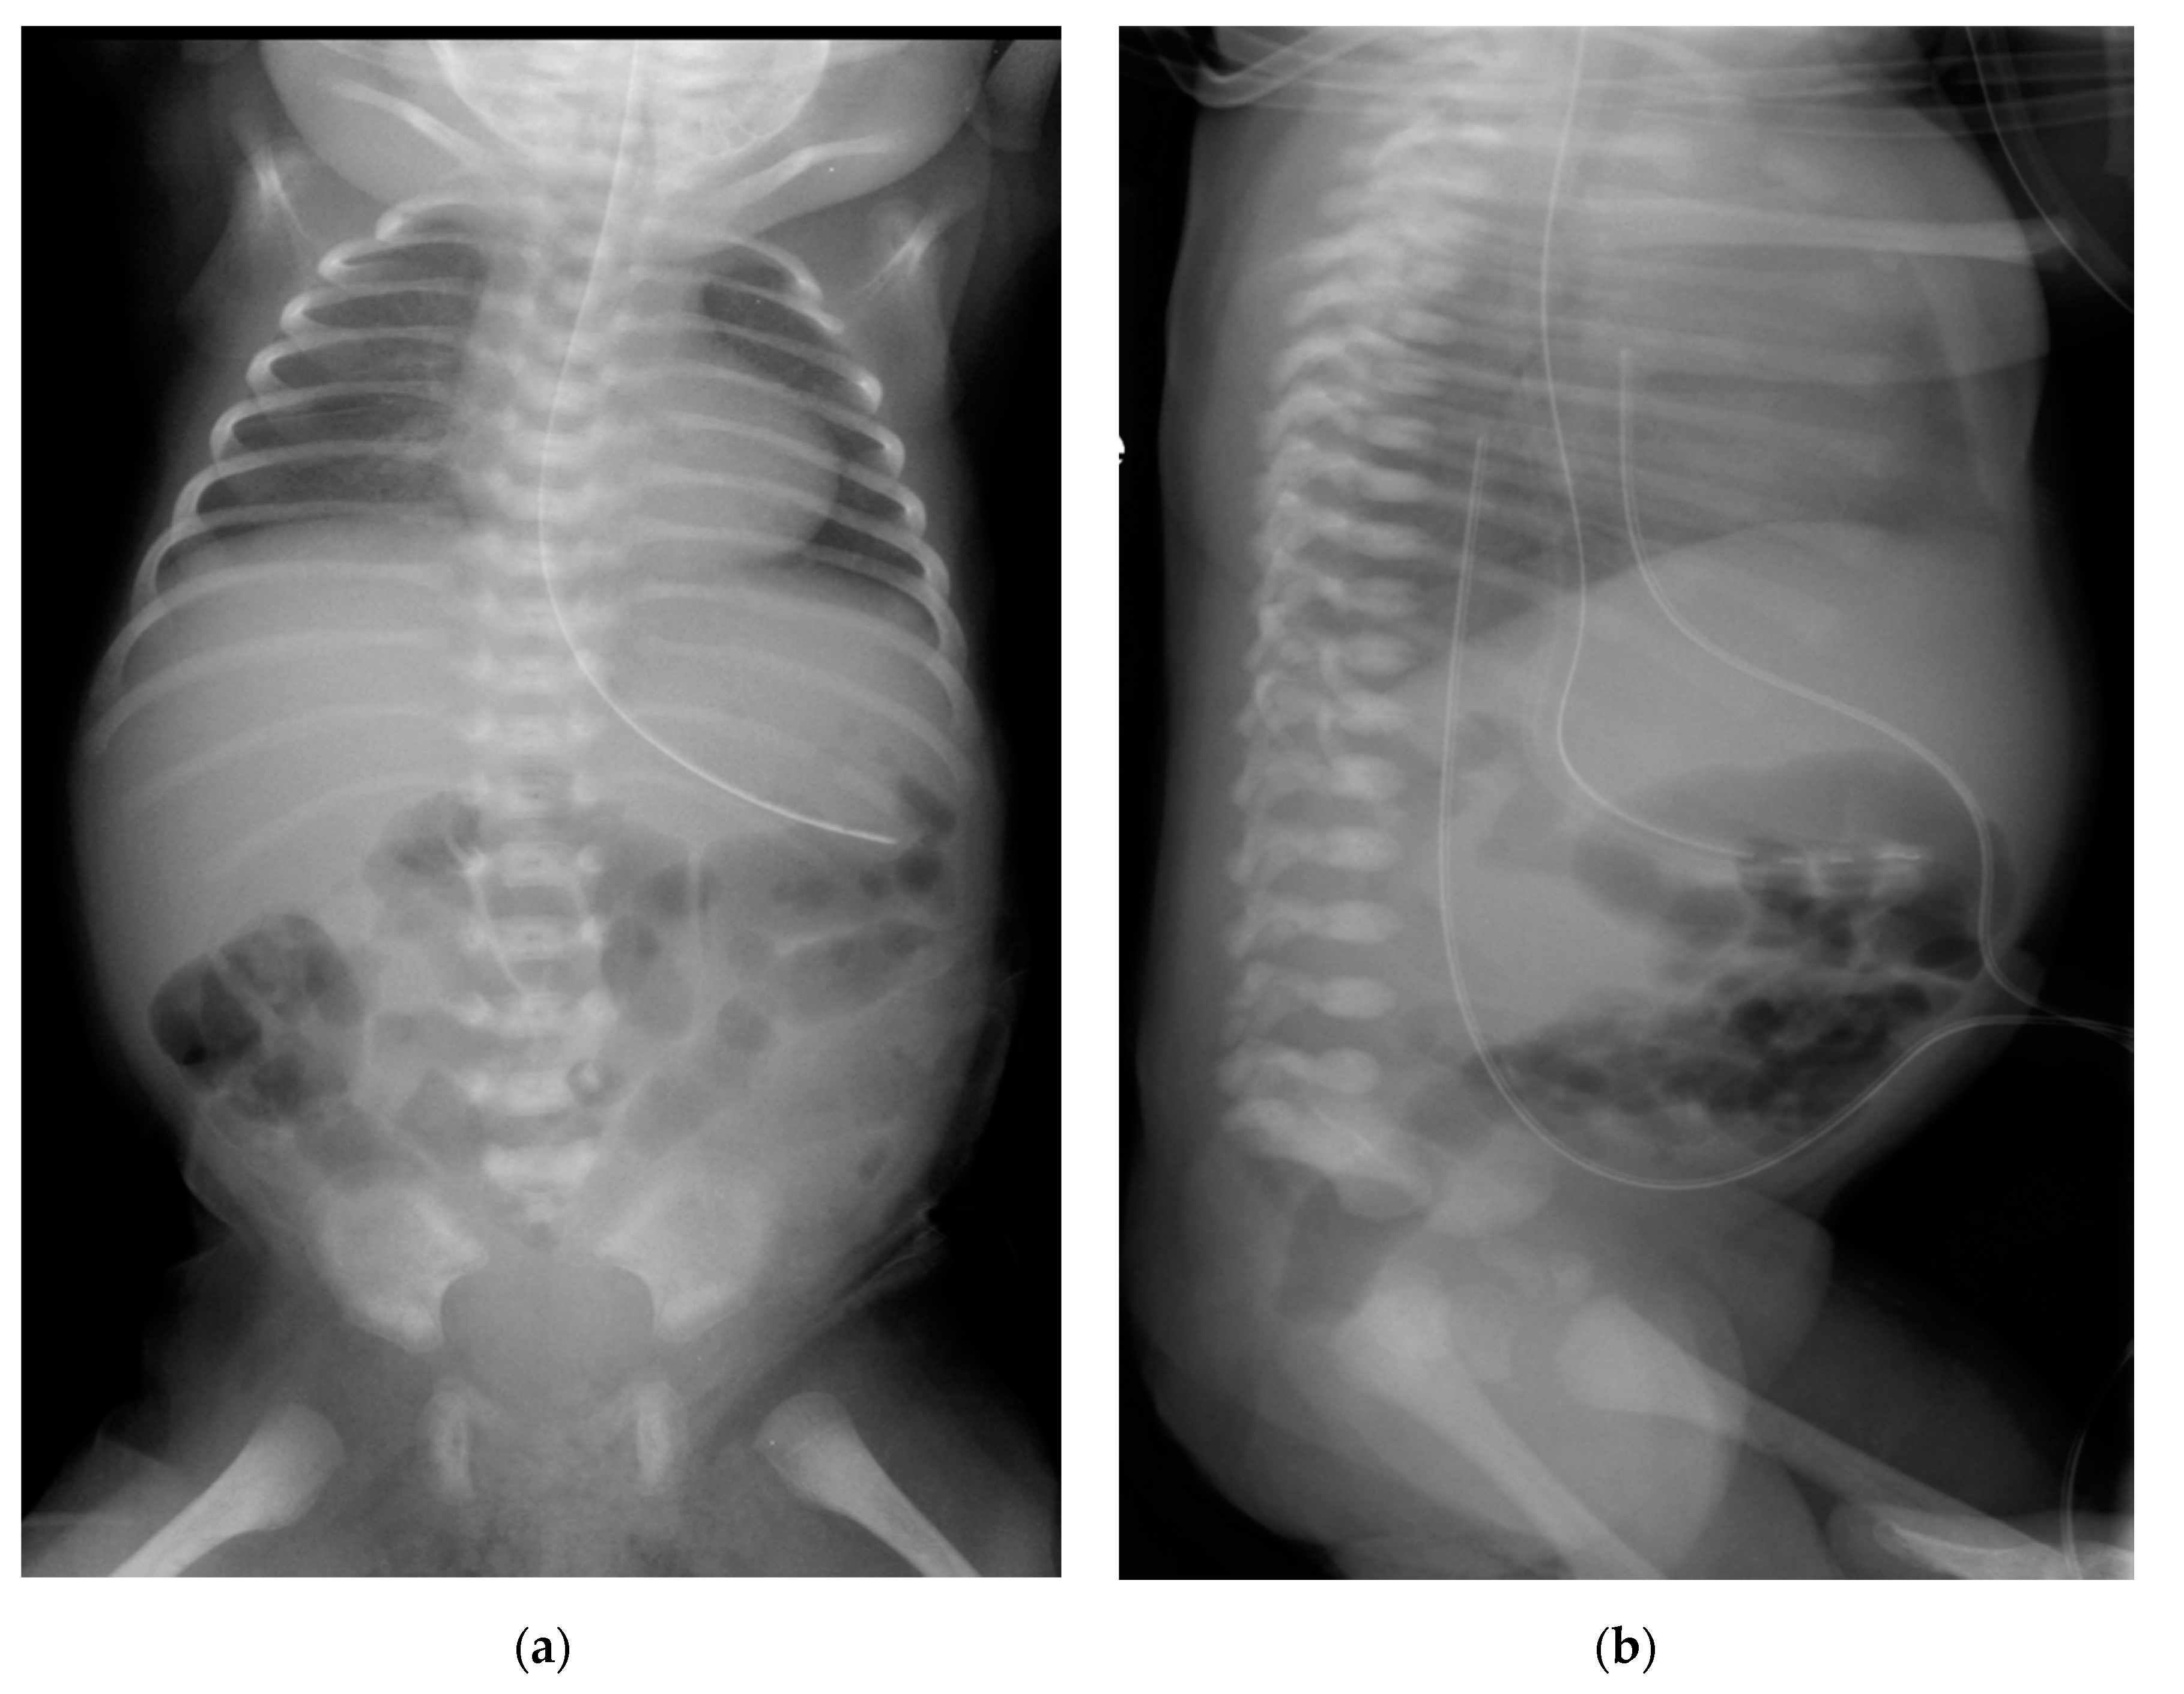

2. Case Presentation